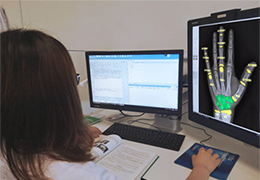

Designed for surgeons, Pro Surgical 3D makes it easy to view patient scans quickly. Pro Surgical 3D facilitates the optimal 3D treatment and assessment workflows based on X-ray CT and MRI scans – and best of all, it’s FREE!

Everyone – including surgeons, patients and their loved ones – benefits from being better informed by the wealth of information buried within CT and MRI scans. Pro Surgical 3D gives surgeons more information to develop optimal treatment plans for patients. It also helps patients and their support group better understand their medical condition and proposed treatment options.

Better understanding of a condition, disease or diagnosis

Ability to clearly see the condition or disease

Better understanding of treatment options